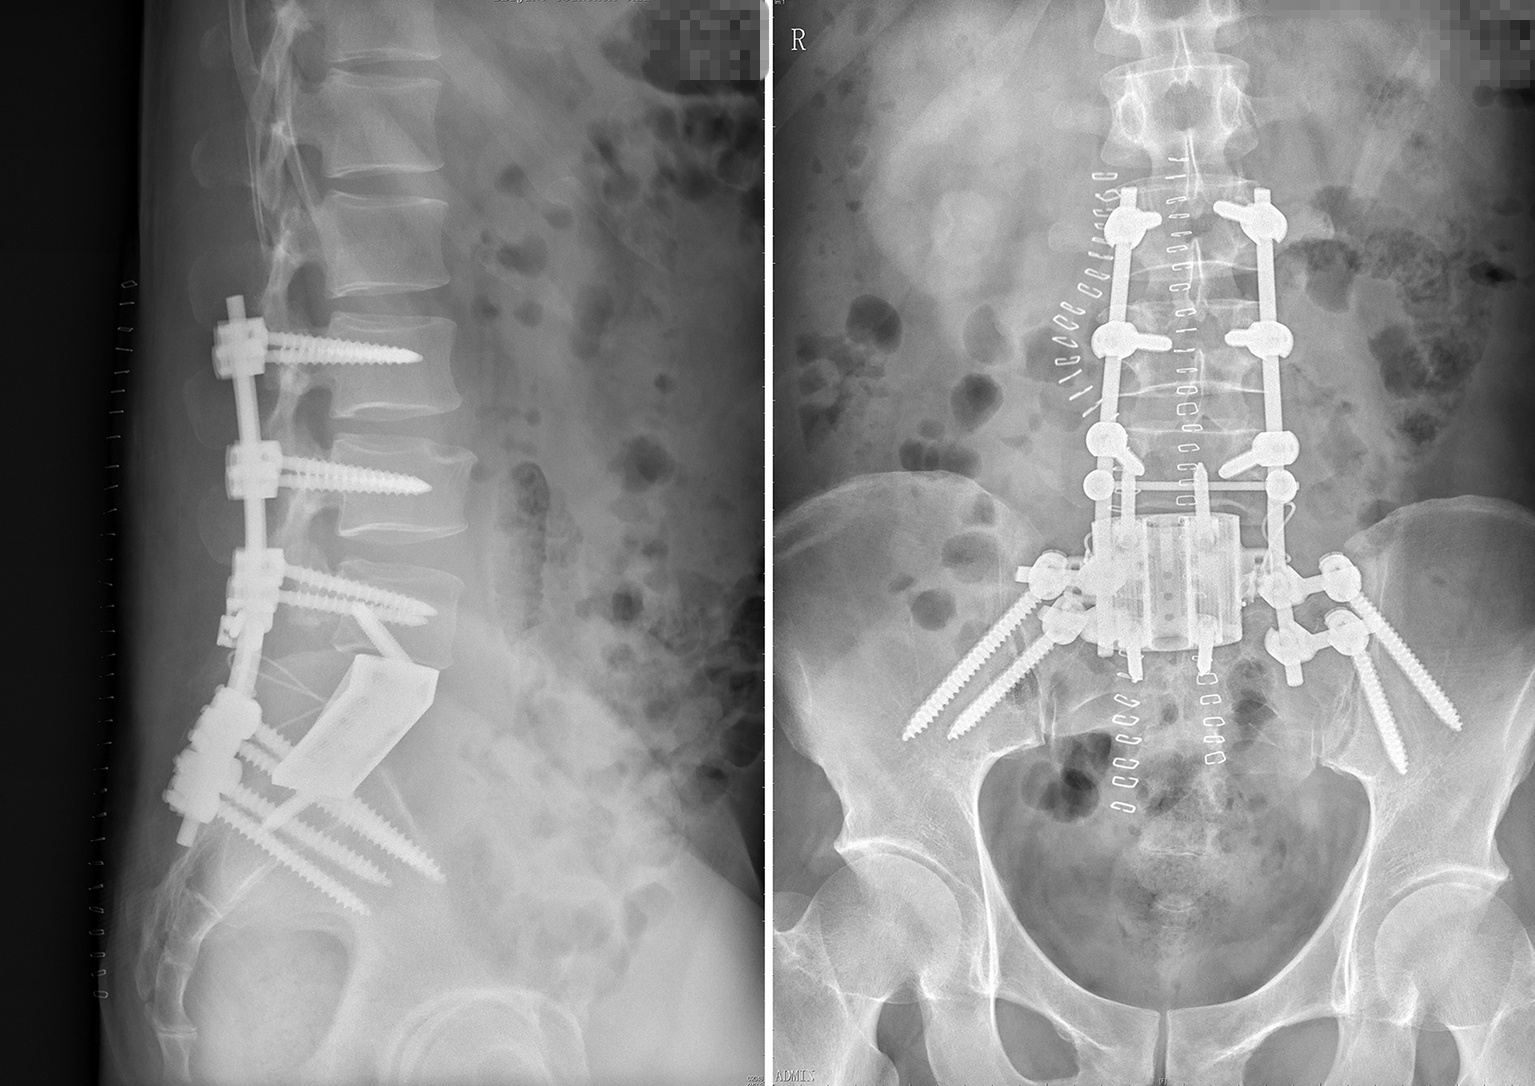

手术在新的一天的凌晨2点结束,术中,跟台护士更换了3批;前后路的转换,患者翻身2次,正常手术历时10余个小时,生命体征未出现波动,患者在ICU病房几小时后即拔管苏醒。术后的患者如厕正常,并已下地活动,复查X光片,内固定位置良好,假体完全贴合。

第三步再次前路,从腹膜后整块切除椎体及被肿瘤包绕的右侧S1神经根一段,并重新搭桥吻合。植入3D打印个体化适型假体,匹配后锁钉固定。

第二步翻身后路,行L345及髂骨螺钉固定,整块切除后方未被累及的椎板,并确定后方截骨平面,前后“会师”。

手术分三步。第一步前路游离保护内脏及血管。开腹经双侧腹膜后分离,保护正常组织,并确定前方截骨平面。上方至L5S1间隙,下方至S2椎体骶孔上缘,两侧至骶髂关节,由此保证整个肿瘤组织完整切除,减少肿瘤复发几率。